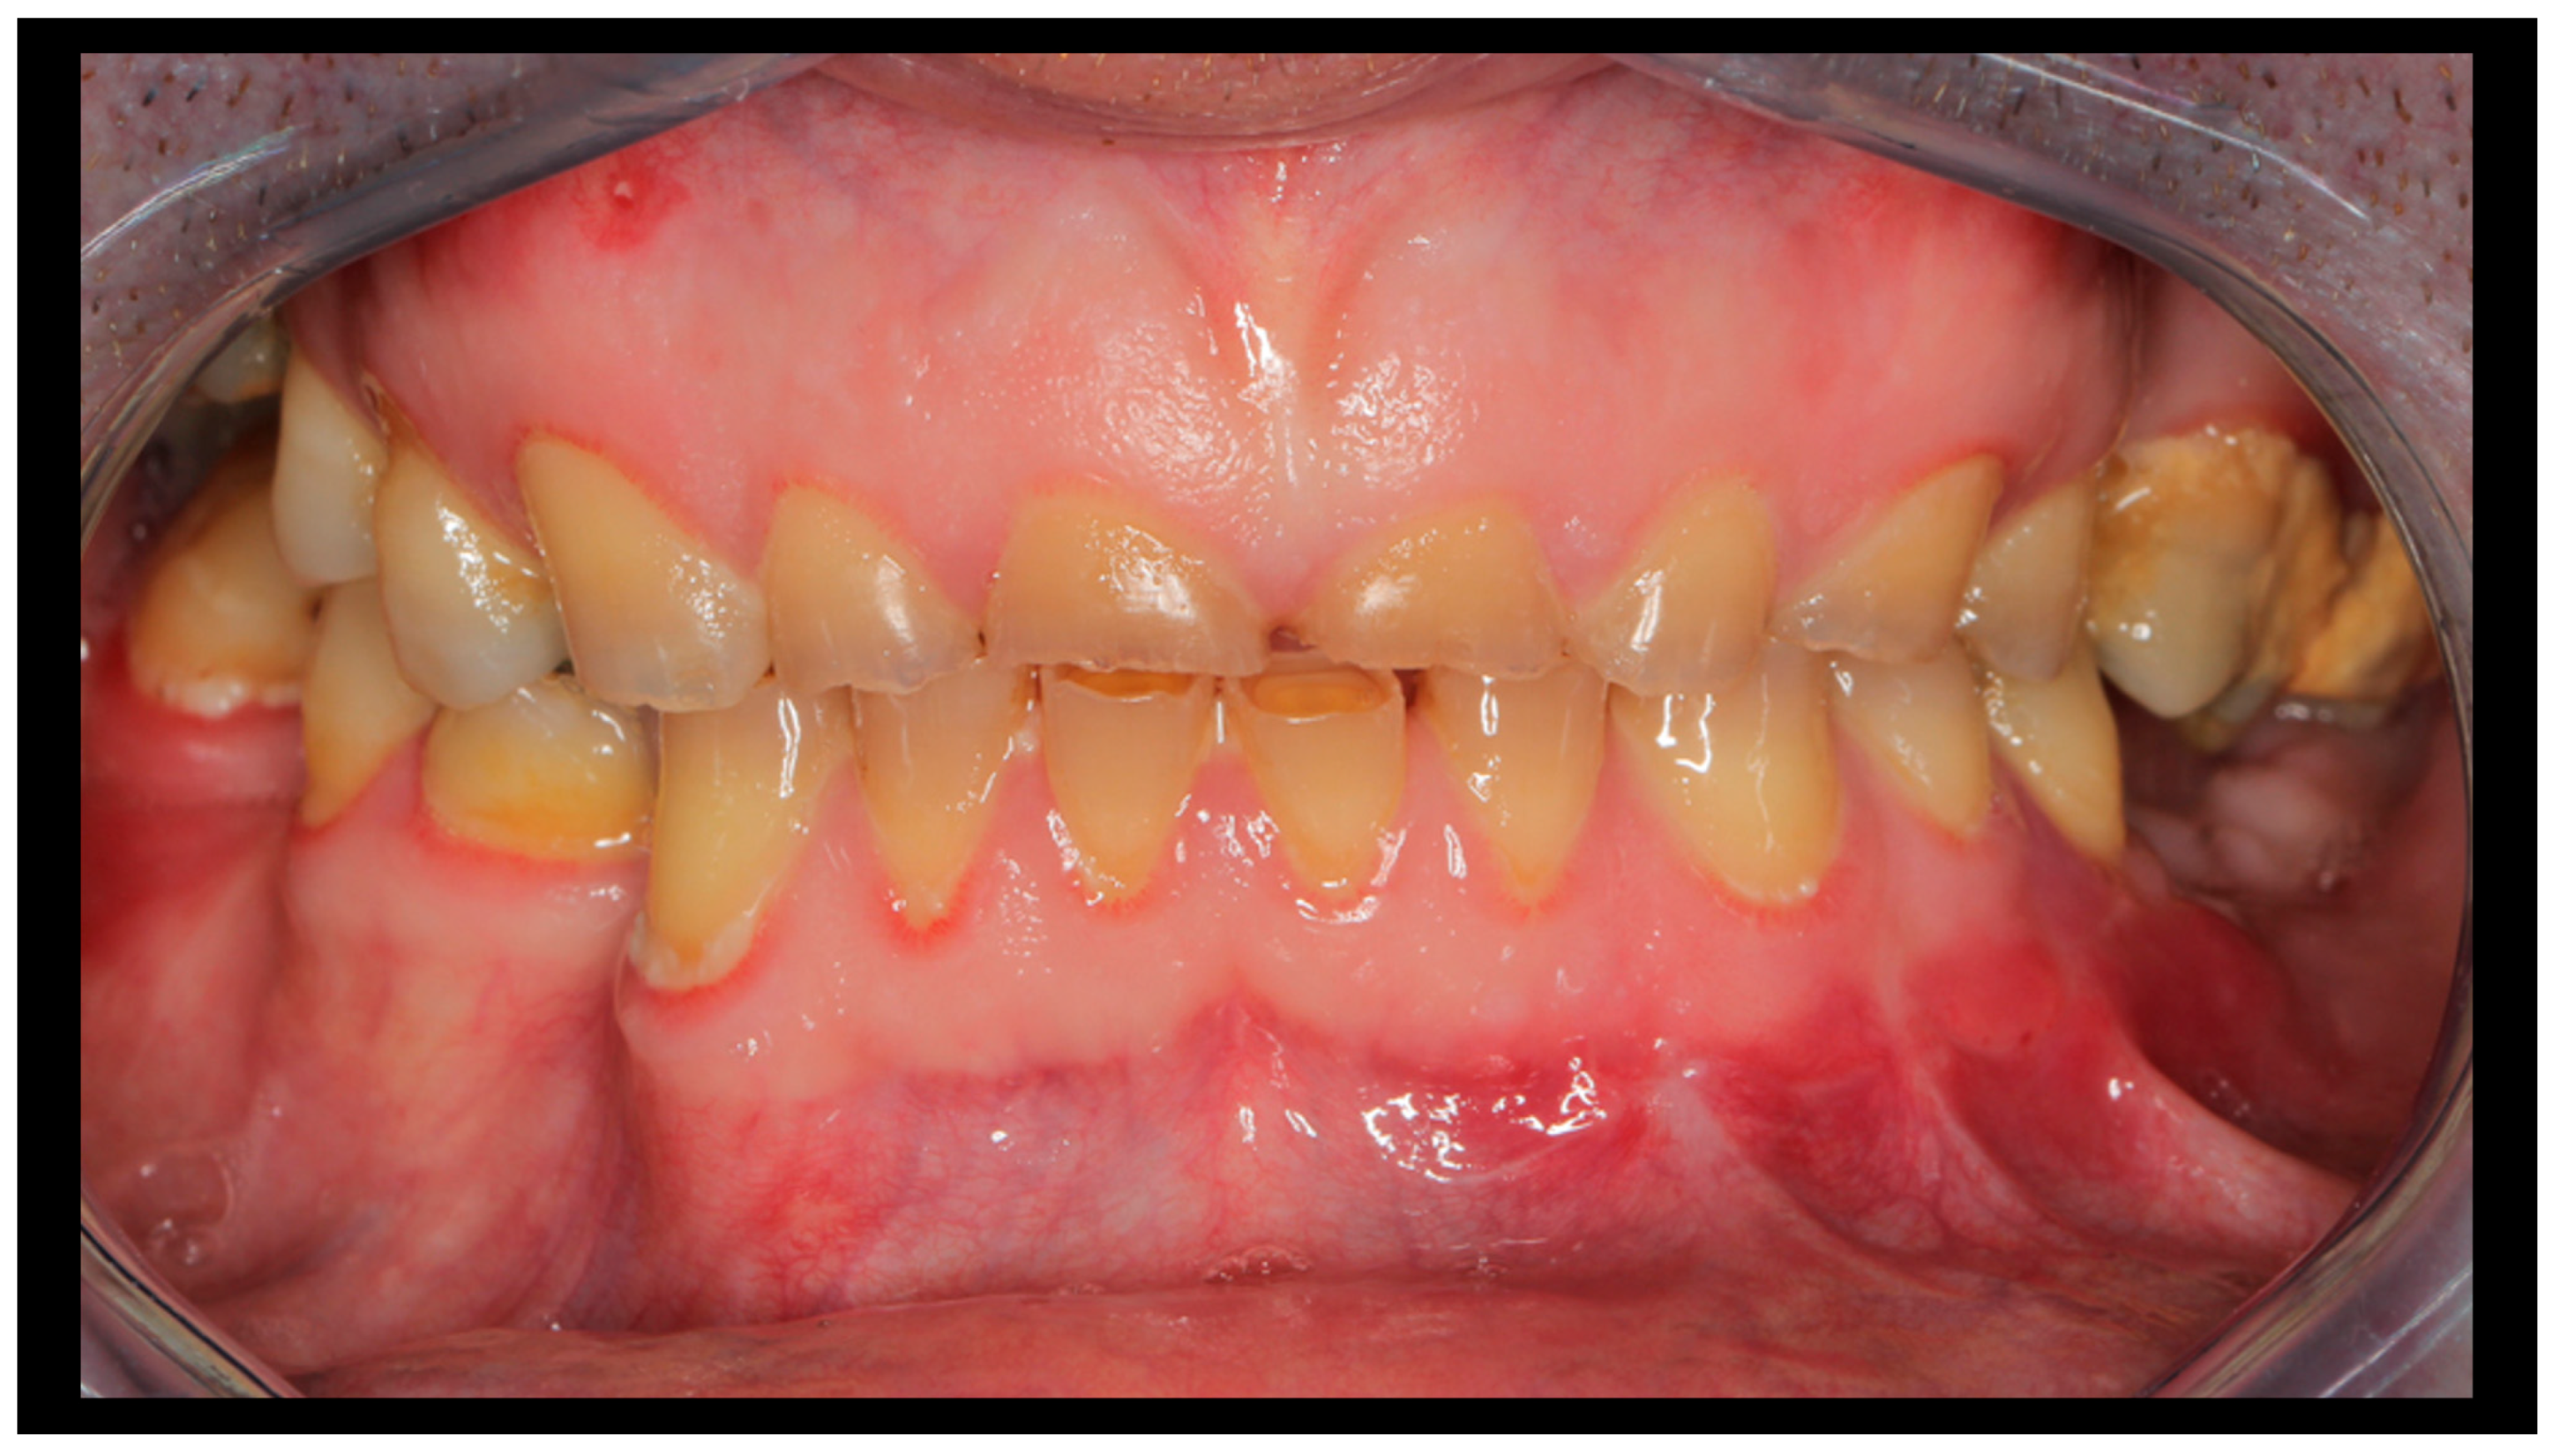

| A. Range of mandibular movement | Normal opening and excursions (MIO ≥ 40 mm, lateral movements ≥ 7 mm) | Slightly reduced opening or lateral movement | Severely restricted mandibular movements |

| B. TMJ function (movement) | Smooth, symmetrical movements | Deviation or clicking during opening/closing | Locking, severe deviation, or crepitus |

| C. Muscle pain on palpation | No pain | Mild tenderness at 1–2 muscle sites | Severe pain in ≥3 muscle sites |

| D. TMJ pain on palpation | No pain | Mild unilateral TMJ pain | Severe or bilateral TMJ pain |

| E. Pain during mandibular movement | No pain | Mild pain during opening/closing | Severe pain during movement |